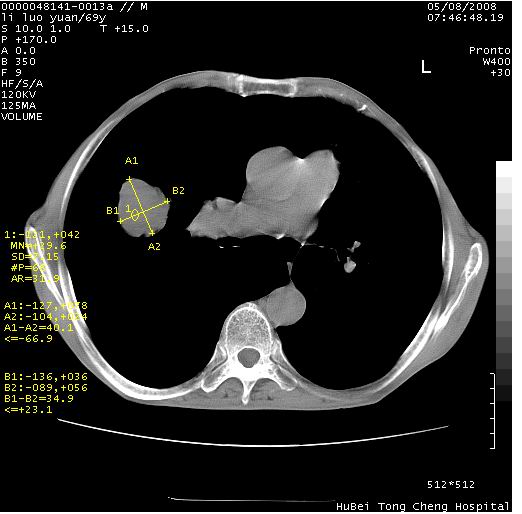

临床资料:老年患者,咯血、消瘦

影像表现:桶状胸,双肺纹理纤细、紊乱,透过度增高,肺野内可见多发、散在、大小不等的无壁高透过影,右肺中叶外侧段分叶样软组织占位,左上肺纤维索条样密度影,相应层面左侧胸腔轻度萎陷,纵隔左移。

影像诊断:1、慢支、肺气肿、双下肺野肺大泡形成

2、左上肺陈旧性肺结核

3、右肺中叶外侧段占位 考虑肺ca可能性较大、建议增强及痰检脱落细胞